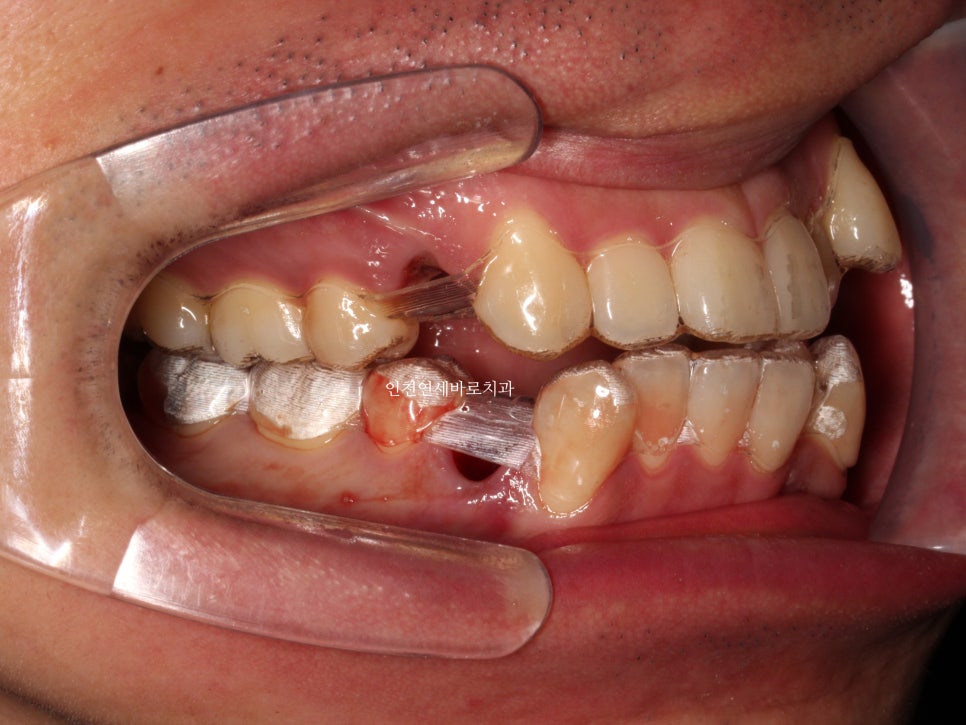

위 2개는 3일전에 발치, 아래 두개는 인비절라인을 시작하는 날 발치하고 바로 장치를 착용했습니다.

약 7개월이 지난 후의 사진인데 벌써 많은 양의 덧니가 해결되었네요